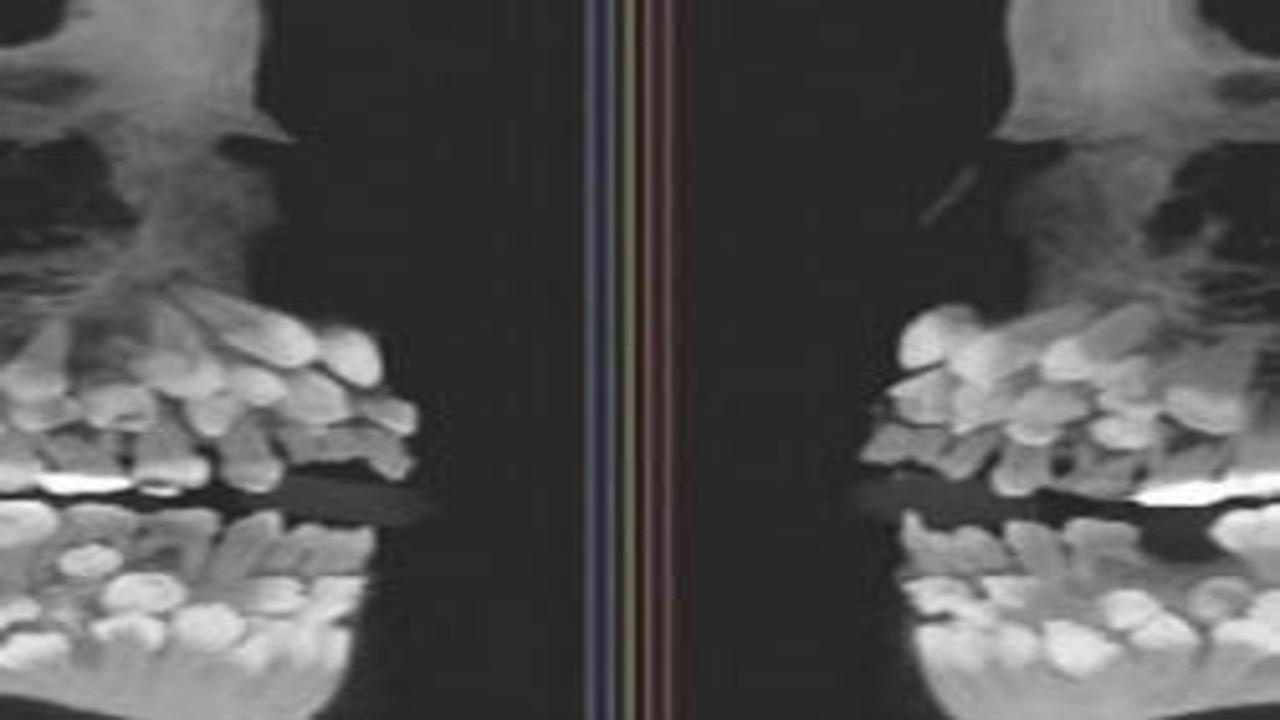

Brezilya'da 11 yaşındaki bir kızın ağzında 81 diş keşfedildi. Normalin çok üzerindeki diş sayısı, tıp dünyasında büyük şaşkınlık yaratarak, uzmanları harekete geçirdi...